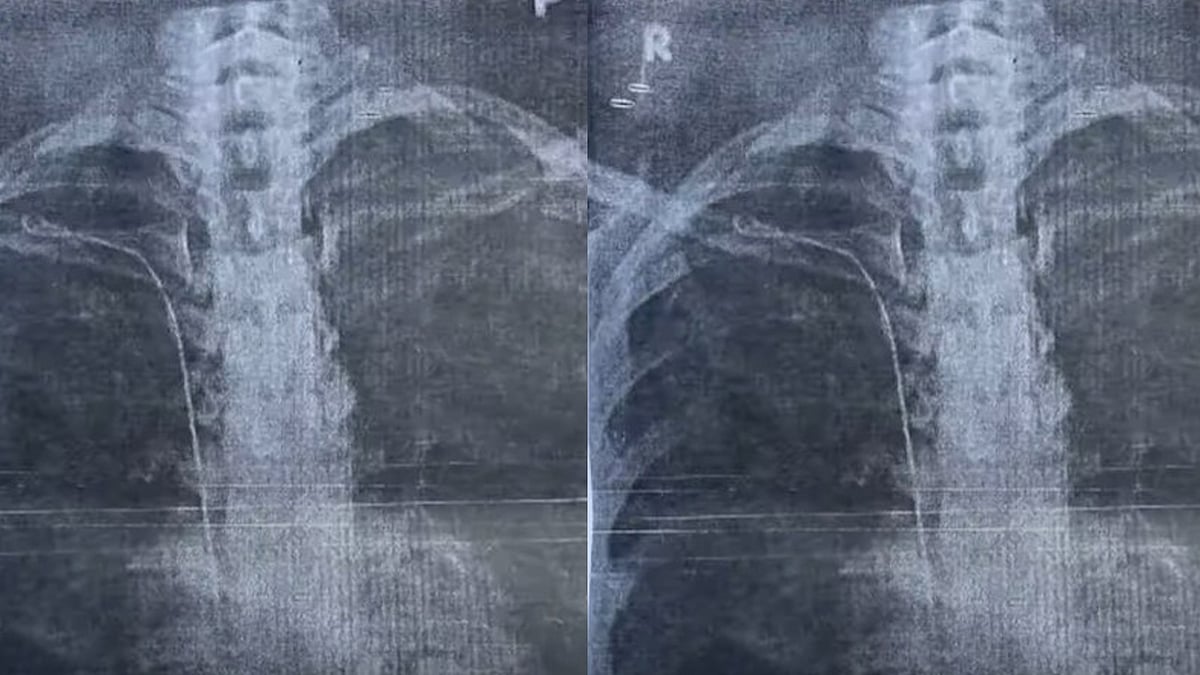

തിരുവനന്തപുരം: തിരുവനന്തപുരം ജനറല് ആശുപത്രിയില് ചികിത്സാപിഴവെന്ന് ആരോപണം. ശസ്ത്രക്രിയയ്ക്കിടെ നെഞ്ചില് സര്ജിക്കല് ട്യൂബ് കുടുങ്ങിയെന്ന ആരോപണവുമായി കാട്ടാക്കട സ്വദേശിയായ യുവതി രംഗത്ത്. 50 സെന്റിമീറ്റര് നീളമുള്ള ട്യൂബ് ആണ് കുടുങ്ങിയത്. ഇതുമായി ബന്ധപ്പെട്ട് യുവതി ആരോഗ്യ വകുപ്പില് പരാതി നല്കി.

2023 മാര്ച്ച് 22ന് നടന്ന തൈറോയ്ഡ് ശസ്ത്രക്രിയയ്ക്കിടെയാണ് ട്യൂബ് കുടുങ്ങിയതെന്നാണ് യുവതിയുടെ പരാതിയില് പറയുന്നത്. ശ്വാസം മുട്ടലിനെ തുടര്ന്ന് നടത്തിയ പരിശോധനയിലാണ് നെഞ്ചില് ട്യൂബ് കിടക്കുന്നതായി അറിഞ്ഞതെന്നും യുവതി പറയുന്നു. ട്യൂബ് നീക്കം ചെയ്യാന് കഴിയാത്ത സാഹചര്യമാണെന്ന് മറ്റ് ഡോക്ടര്മാര് അറിയിച്ചതായും യുവതി പറയുന്നു.